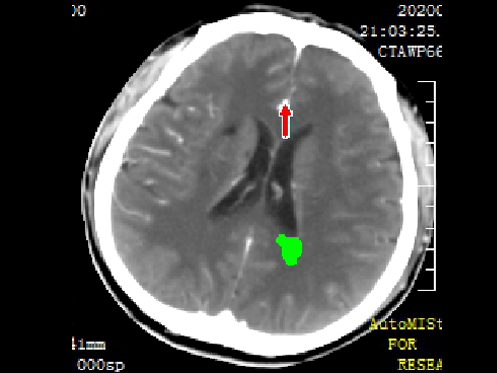

入院头CT

急诊予以静脉溶栓,同时完善头颈CTA+CTP、MIStar相关检查

结合CTA结果,提示左侧颈内动脉起始部至颈内动脉末端未见显影,起始部成鼠尾征改变,前交通动脉开放,双侧大脑中动脉显影良好。MIStar图像提示核心梗死灶和缺血半暗带较小,但是MTT提示左侧大脑中动脉流域区明显延长。